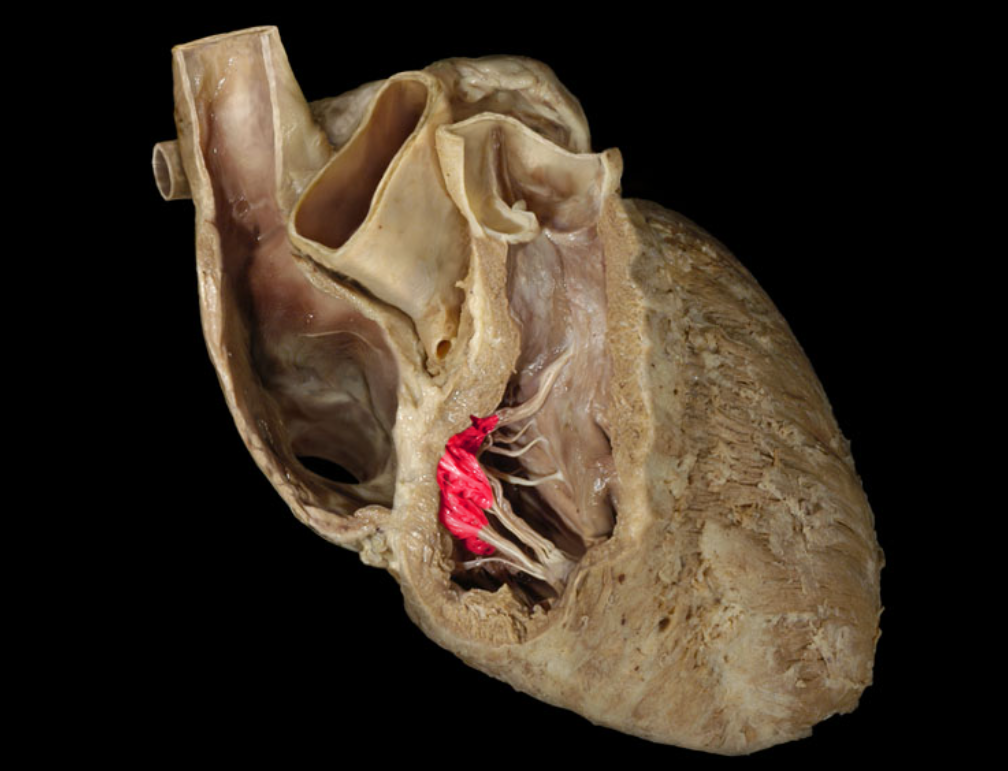

Chordae tendineae

Left atrioventricular valve

Right atrioventricular valve